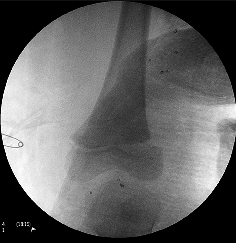

Hip dislocation

Posterior dislocations account for 80% of hip traumas. Low energy injuries cause traumatic hip dislocations in the younger child (2–5 years) due to associated ligamentous laxity. In older children (11–15years), dislocated hips are caused by higher energy injuries and have a higher association with acetabular fractures, although this is rare. Dislocations are more common than fractures in the paediatric population.

Clinically

- Posterior dislocation:Typically flexed, adducted, internally rotated hip.

- Anterior dislocation:Typically extended, abducted, externally rotated hip.

Conduct a careful neurovascular evaluation with particular attention to the sciatic nerve. Ipsilateral femoral shaft fracture should be excluded before manipulation.

Investigations

If an acetabular fracture is identified on the pre- or post-reduction X-rays, Judet (45° obturator and iliac oblique) views should be obtained. If an intra-articular fragment or incongruent reduction is present, a CT scan is indicated.

Treatment

Exclude an ipsilateral femur fracture before reduction. Assess neurovascular status (especially sciatic nerve function) both before and after reduction. Acutely, attempt closed reduction under procedural sedation, as this is usually successful. In delayed or neglected cases, traction for 3–6 days should be attempted before open reduction if an initial attempt of closed reduction was unsuccessful. Once the hip is reduced, immobilise in traction for 4–6 weeks.

Open reduction is rarely necessary; surgical intervention is indicated in:

- Failed closed reduction

- Nonconcentric reduction

- Displaced acetabular fractures

- Intra-articular fragments

- Sciatic nerve palsy occurring post- reduction where it was normal before reduction.

Dislocated hip. Available from:

https://commons.wikimedia.org/wiki/File:Dislocated_hip.jpg